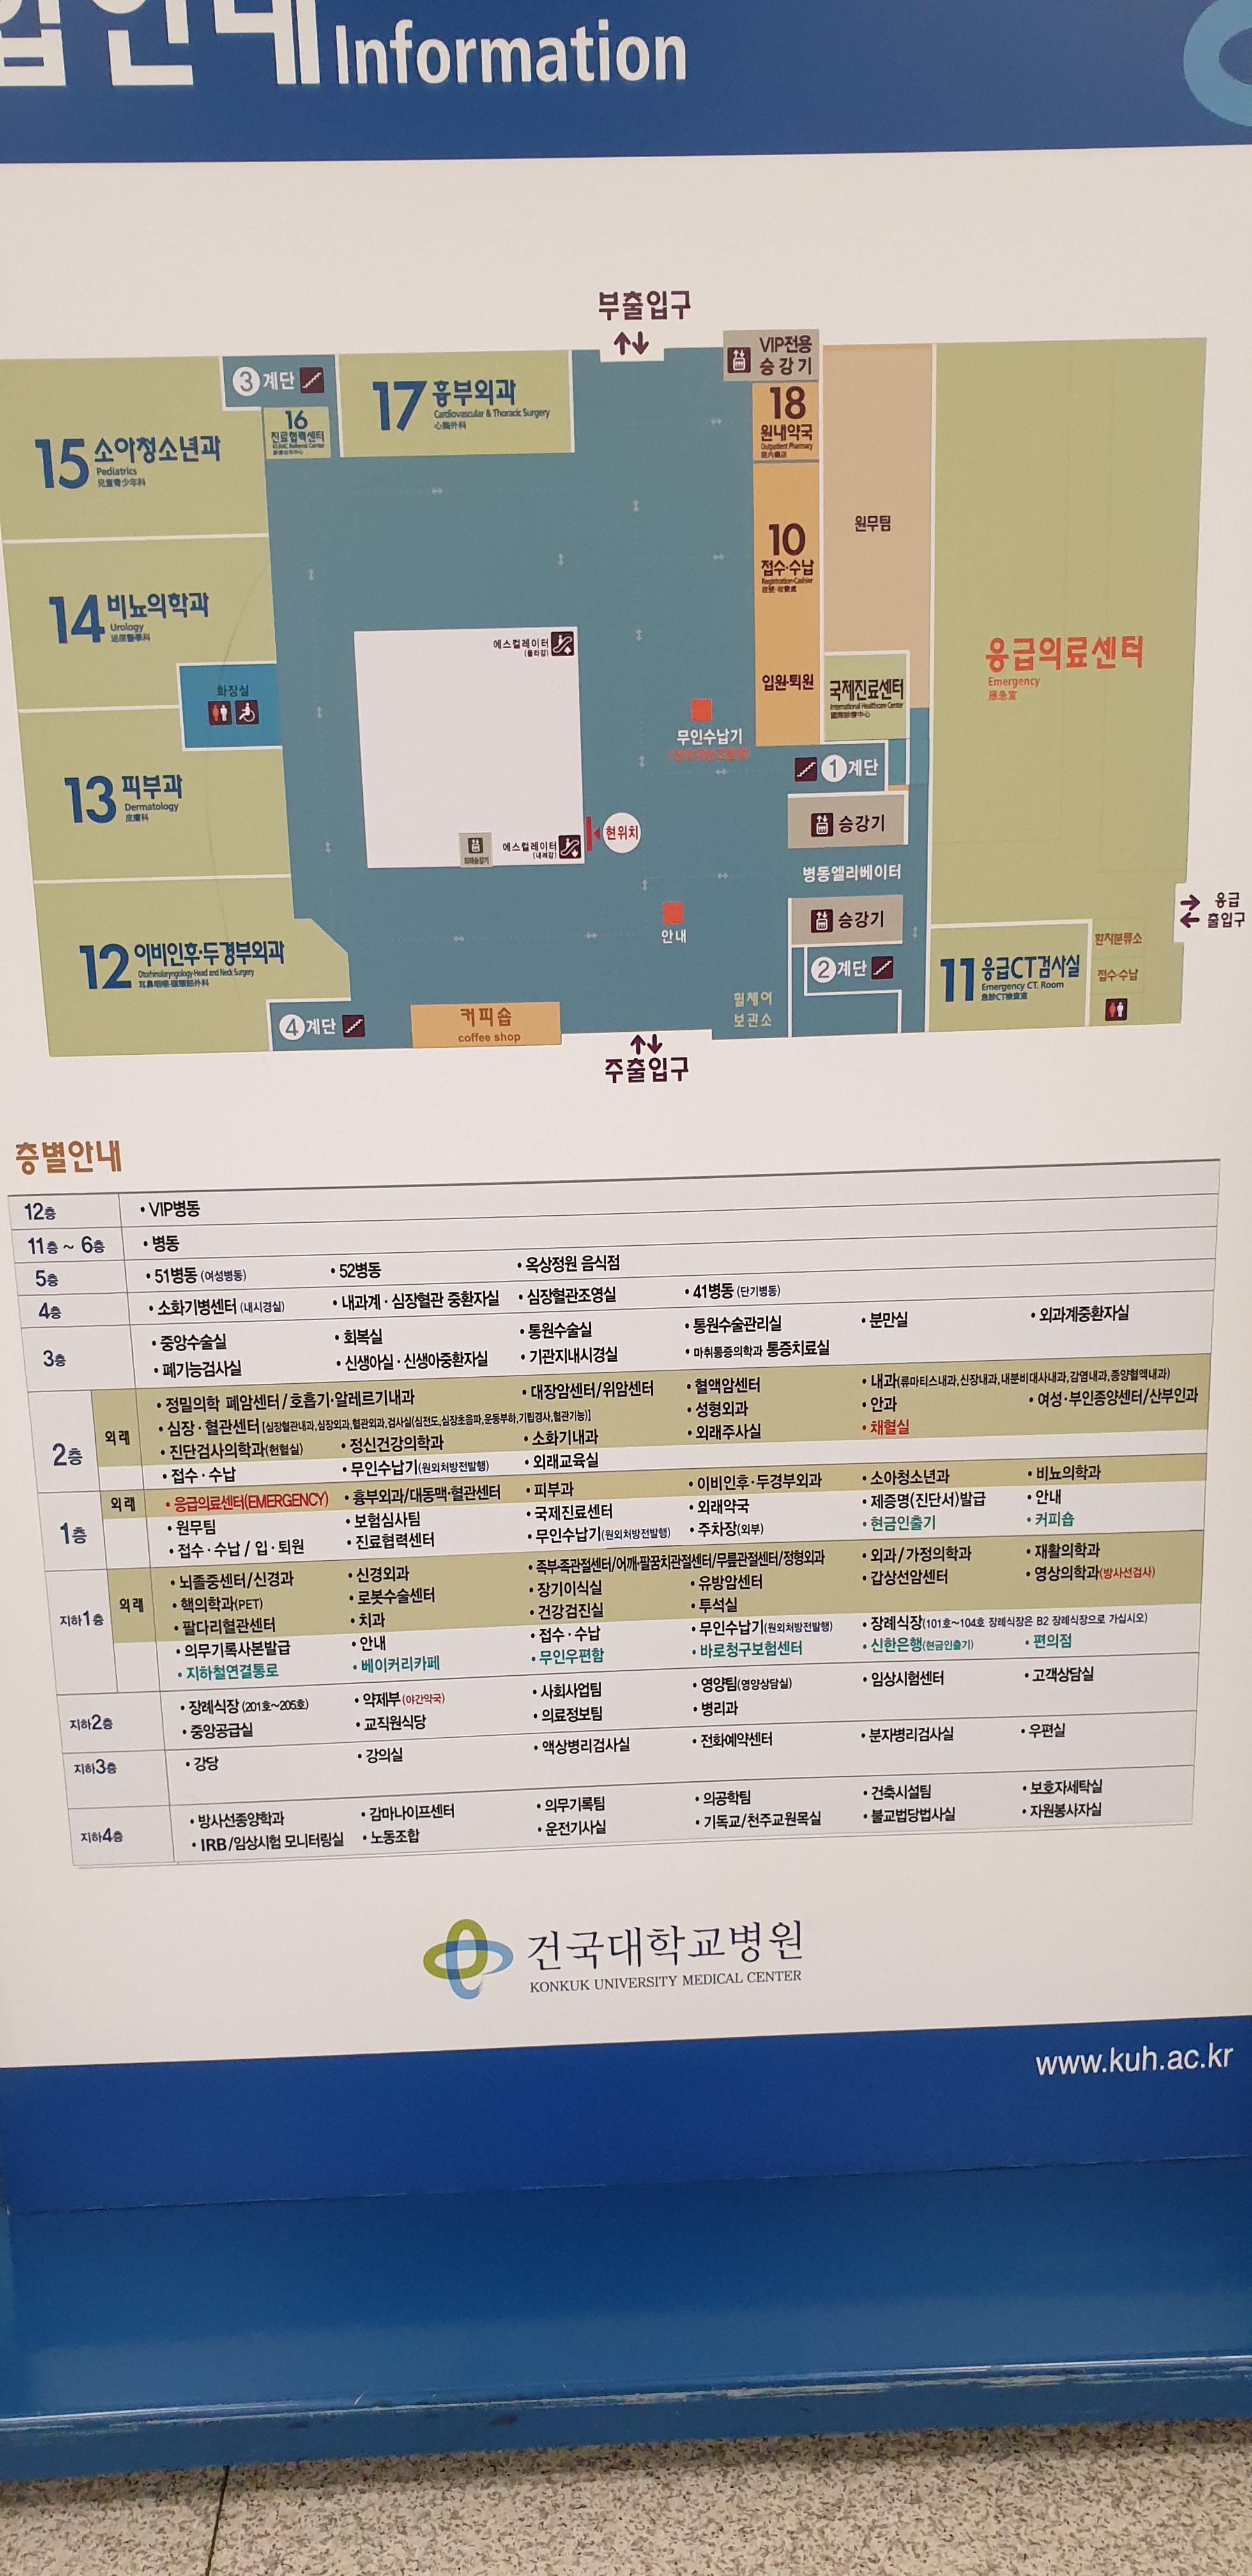

5층 옥상에서 보는 건국대 모습이다.

5층 옥상정원

안내도

힐체어를 타고 지하층 1층 5층을 오간다.

지하층 한바퀴 1층 한바퀴 5층 옥상정원.....